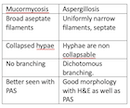

Ans to previous (November 2024):

Fungal filaments consistent with Mucormycosis. Hyphae are broad and non septate , no branching seen to suggest aspergillus filaments.